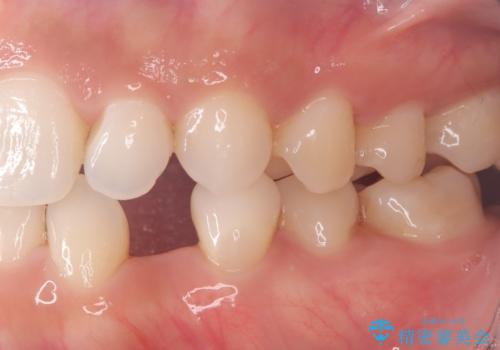

欠損歯をブリッジにて補綴

矯正治療にてスペースを一箇所に集めてからオールセラミックブリッジにて補綴治療を行いました。

今回は、患者様の希望もありインプラントではなくブリッジにて修復しています。